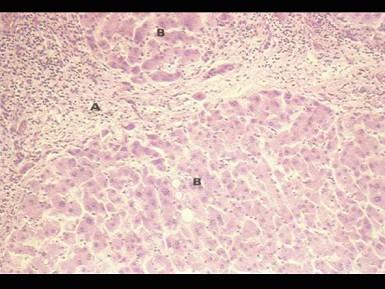

问题 如图所示,急性重型肝炎的主要病理变化是 ( )

选项 A.毛细胆管淤胆 B.肝细胞灶性坏死 C.汇管区结缔组织增生 D.肝小叶及汇管区单核细胞浸润 E.肝细胞广泛性坏死

答案 E